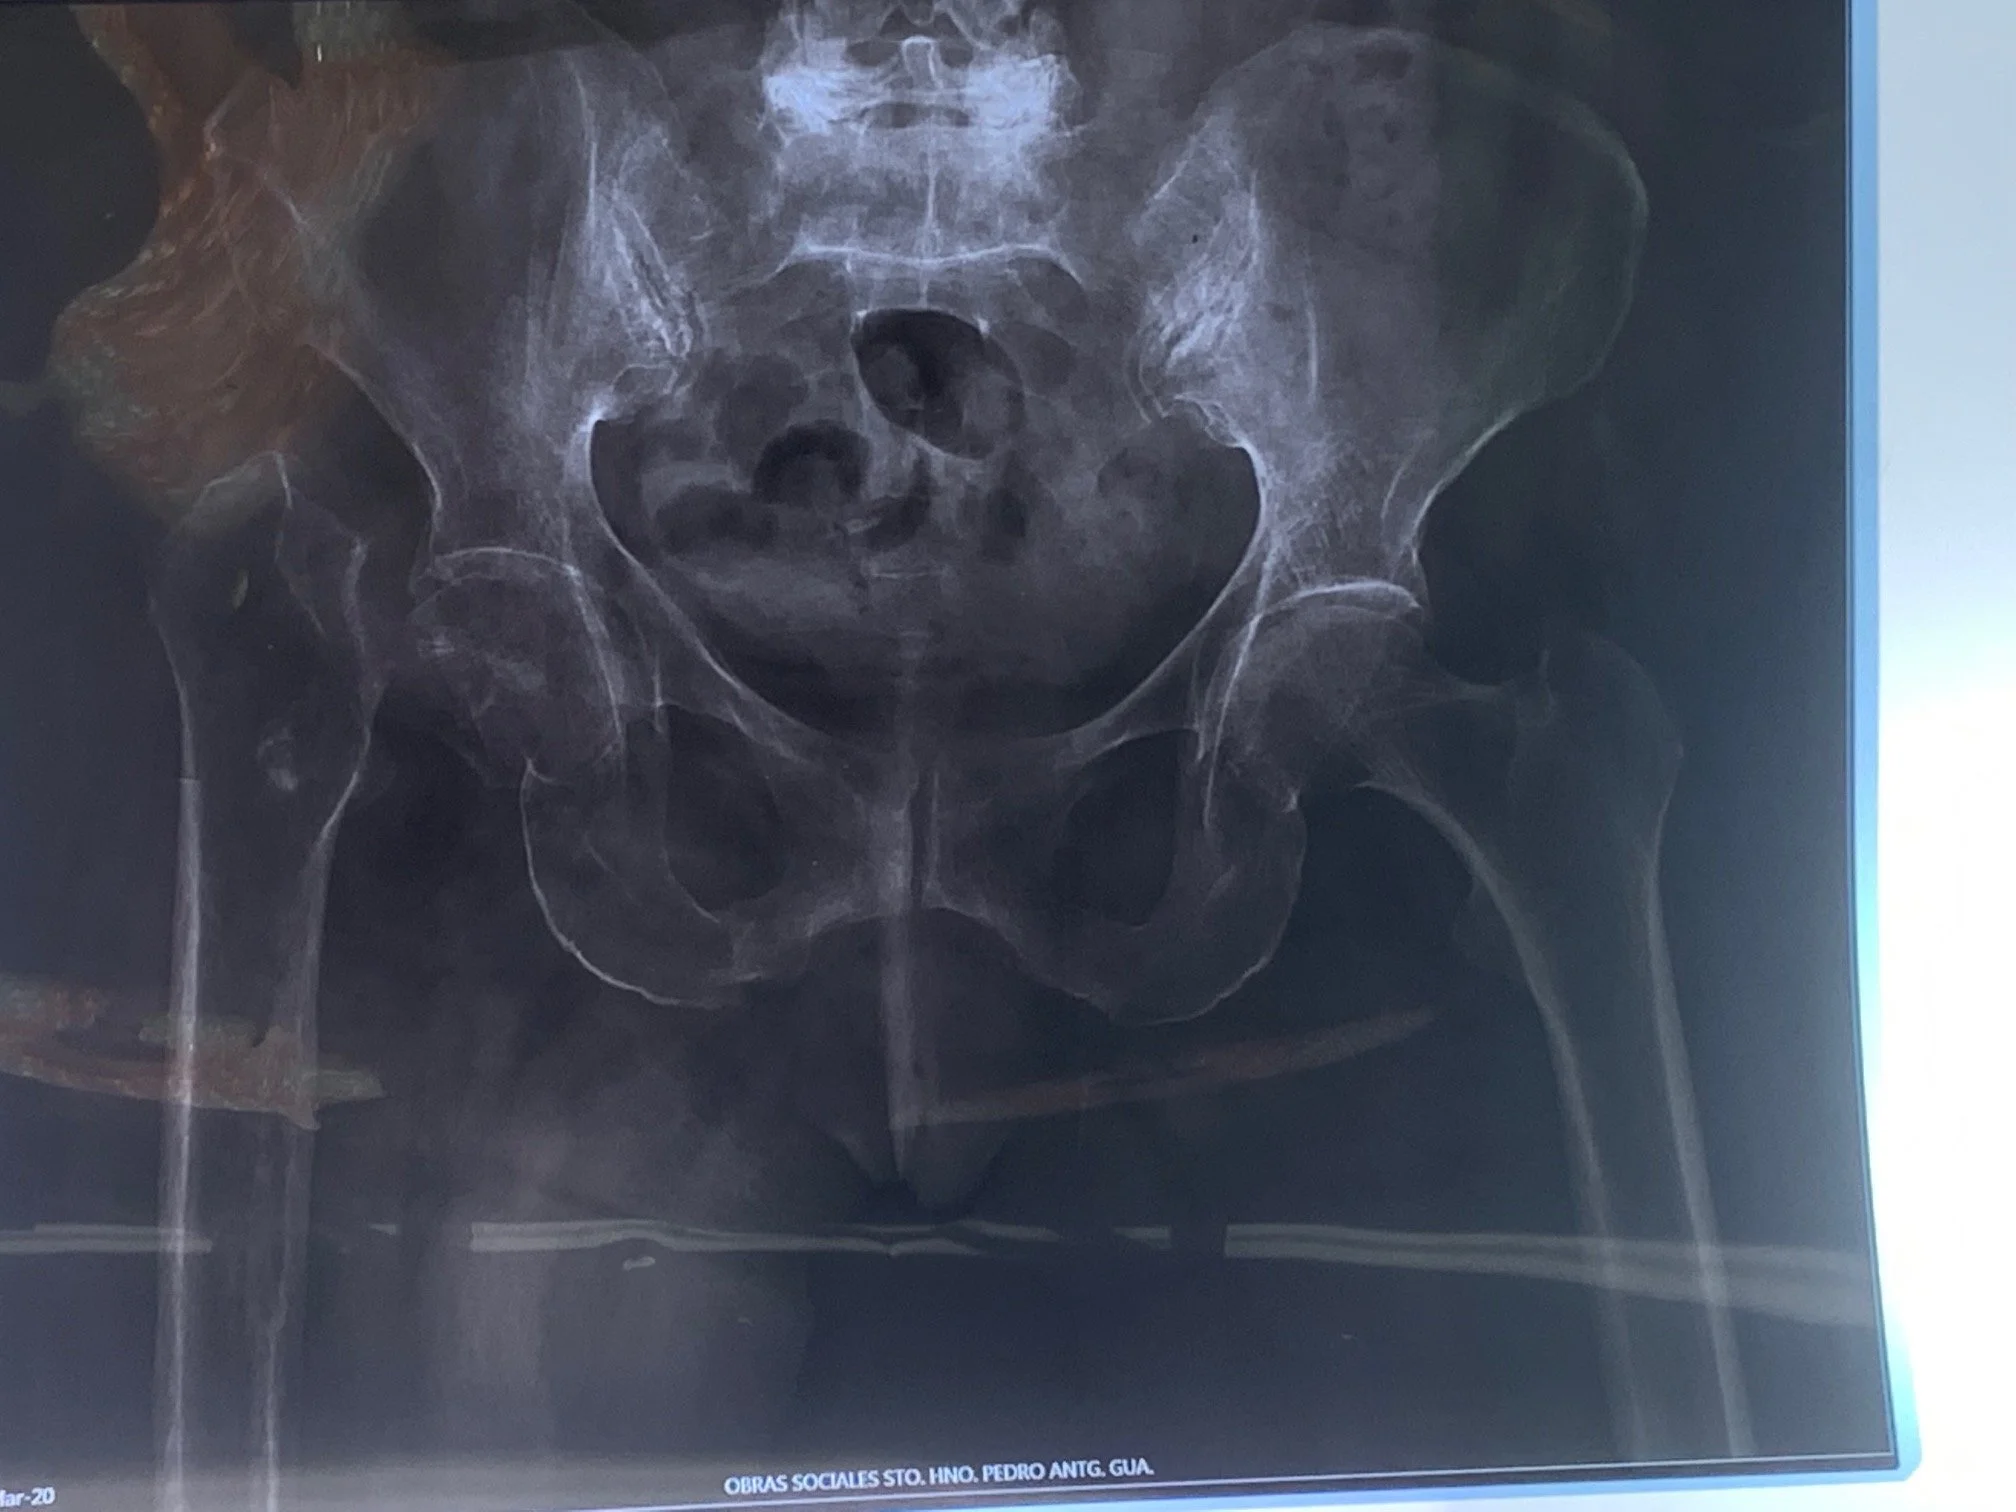

On the hip side, several patients have experienced hip fractures that have been untreated sometimes for several years, making it very difficult, if not impossible for them to walk, and also adding significant surgical challenges for Dr. Keith to repair their condition. Many significant leg length inequalities were improved, and Zimmer Biomet implants were installed to restore motion to these compromised patients. The last hip of the day was an existing total hip that was infected. These cases require removal of existing implants and special hospital protocols to isolate the infected tissue to a controlled section of the operating room area. This included the operating room staff to completely change their garments immediately after the procedure and the patient to go through surgical recovery in the operating room to allow the room to be completely disinfected after the procedure.

Drs. Klaassen and Mike Berend each did multiple total knees, some of which were complex due to unique anatomy. Poor bone quality is a recurrent theme as many of the patients with knee arthritis have learned to walk by favoring their healthy knee and as we all know, if you don’t use it you loose it. Now that they have new knees, and their mobility will be restored, hopefully their bodies will start to generate good bone quality for a more healthy life!! Drs. Herbst and Knecht were hard at work treating a wide variety of foot and ankle disorders. You can see many examples of unusual feet from the pre-op images that have been skillfully reconstructed to their normal anatomical positions.